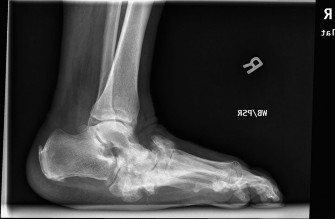

A healthy 43-year-old female developed insidious onset of plantar right heel pain 2 months ago. She describes…